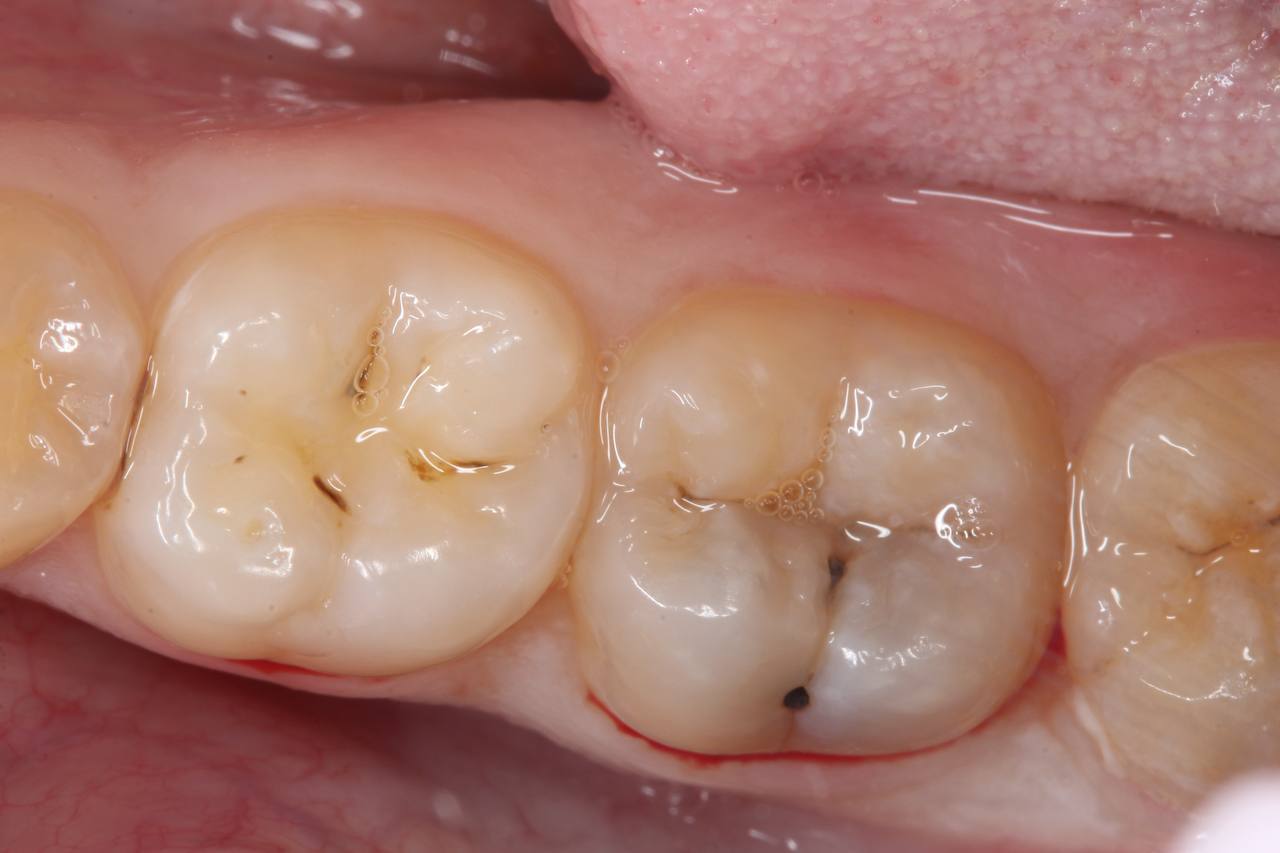

1. анестезия, препарирование кариозной полости

2. восстановление композитным материалом анатомической формы зуба

Результат

Здоровые, функциональные зубы